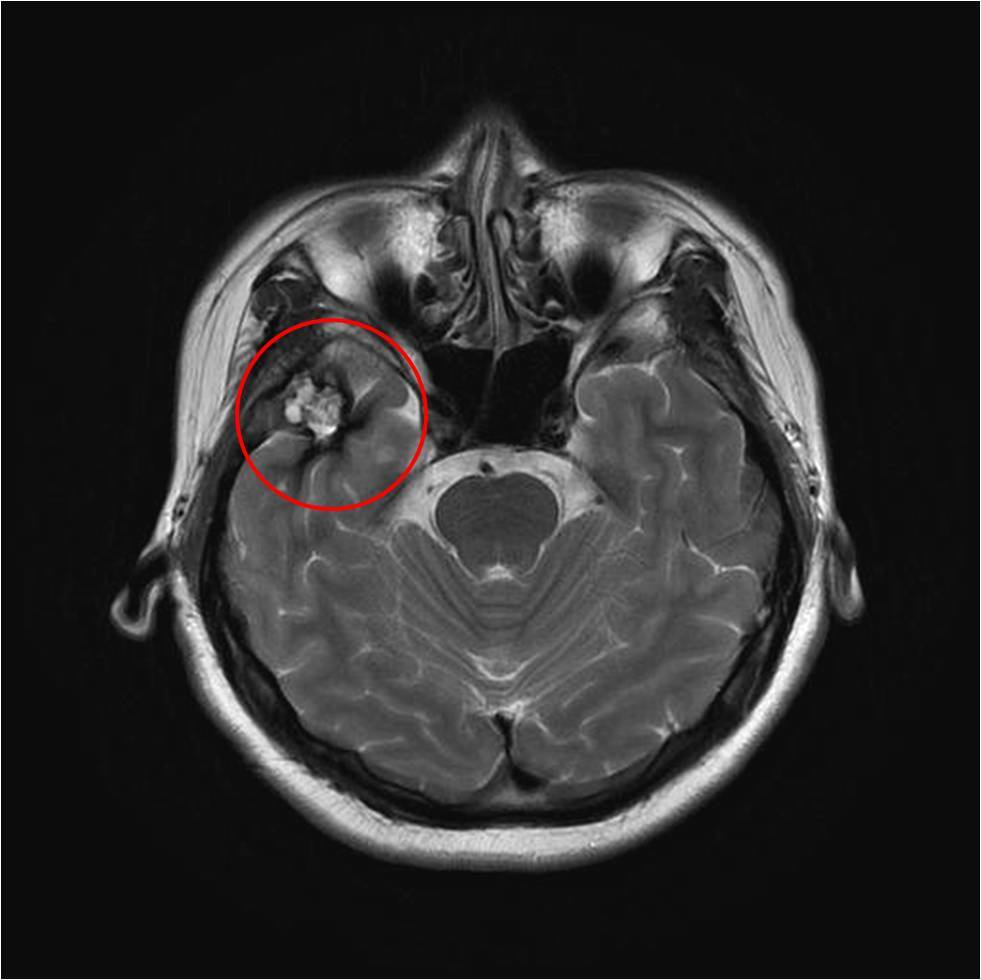

头部磁共振,右侧颞极病变,考虑海绵状血管瘤。

脑电图:背景,漫波,脑区性,右颞部;间歇放电为右颞区,棘慢波。

诊断:继发性癫痫,右侧颞叶海绵状血管瘤

综合分析:患者诊断明确,发作形式和脑电图均支持右侧颞区,考虑导致癫痫发作的直接因素为右颞叶的海绵状血管瘤,这种血管瘤的主要临床表现为癫痫发作,可以手术切除,估计术后痊愈的可能性非常大。但术中需要扩大切除血管瘤周边的含铁血黄素,也是导致癫痫发作的主要脑组织。术中可以用皮层脑电检测,定位皮层放电。